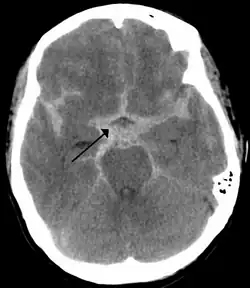

![]() CT-scanning, der viser en subaraknoidal blødning (det hvide område ved pilen) | |